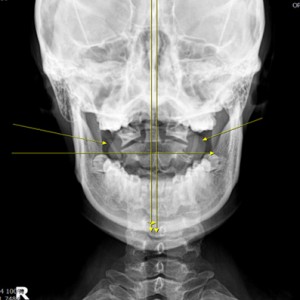

안면 두개골 엑스레이 검사

Submento Vertex View 포함

Catch Point 01. 안면비대칭

X·Y·Z축을 바로 잡는 안면비대칭 3D 입체교정

미간, 콧대, 턱, 목선 맞추기

눈썹 높이 수평

입꼬리 수평

두상 위치 균형

어깨 비대칭 개선